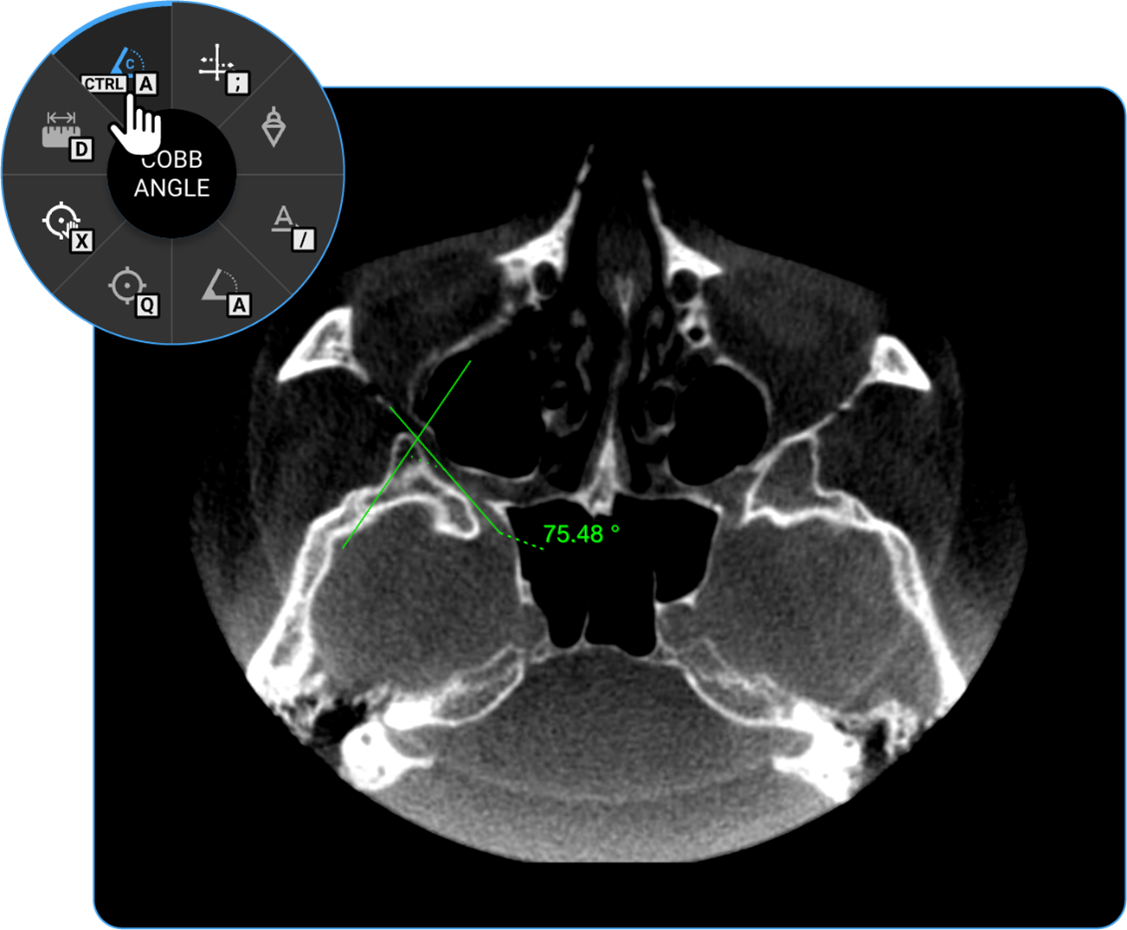

1. Cobb Angle: Locate the Cobb Angle tool on the adjustment wheel and click on it to measure the degree of spinal curvature, aiding in scoliosis assessment.

vai